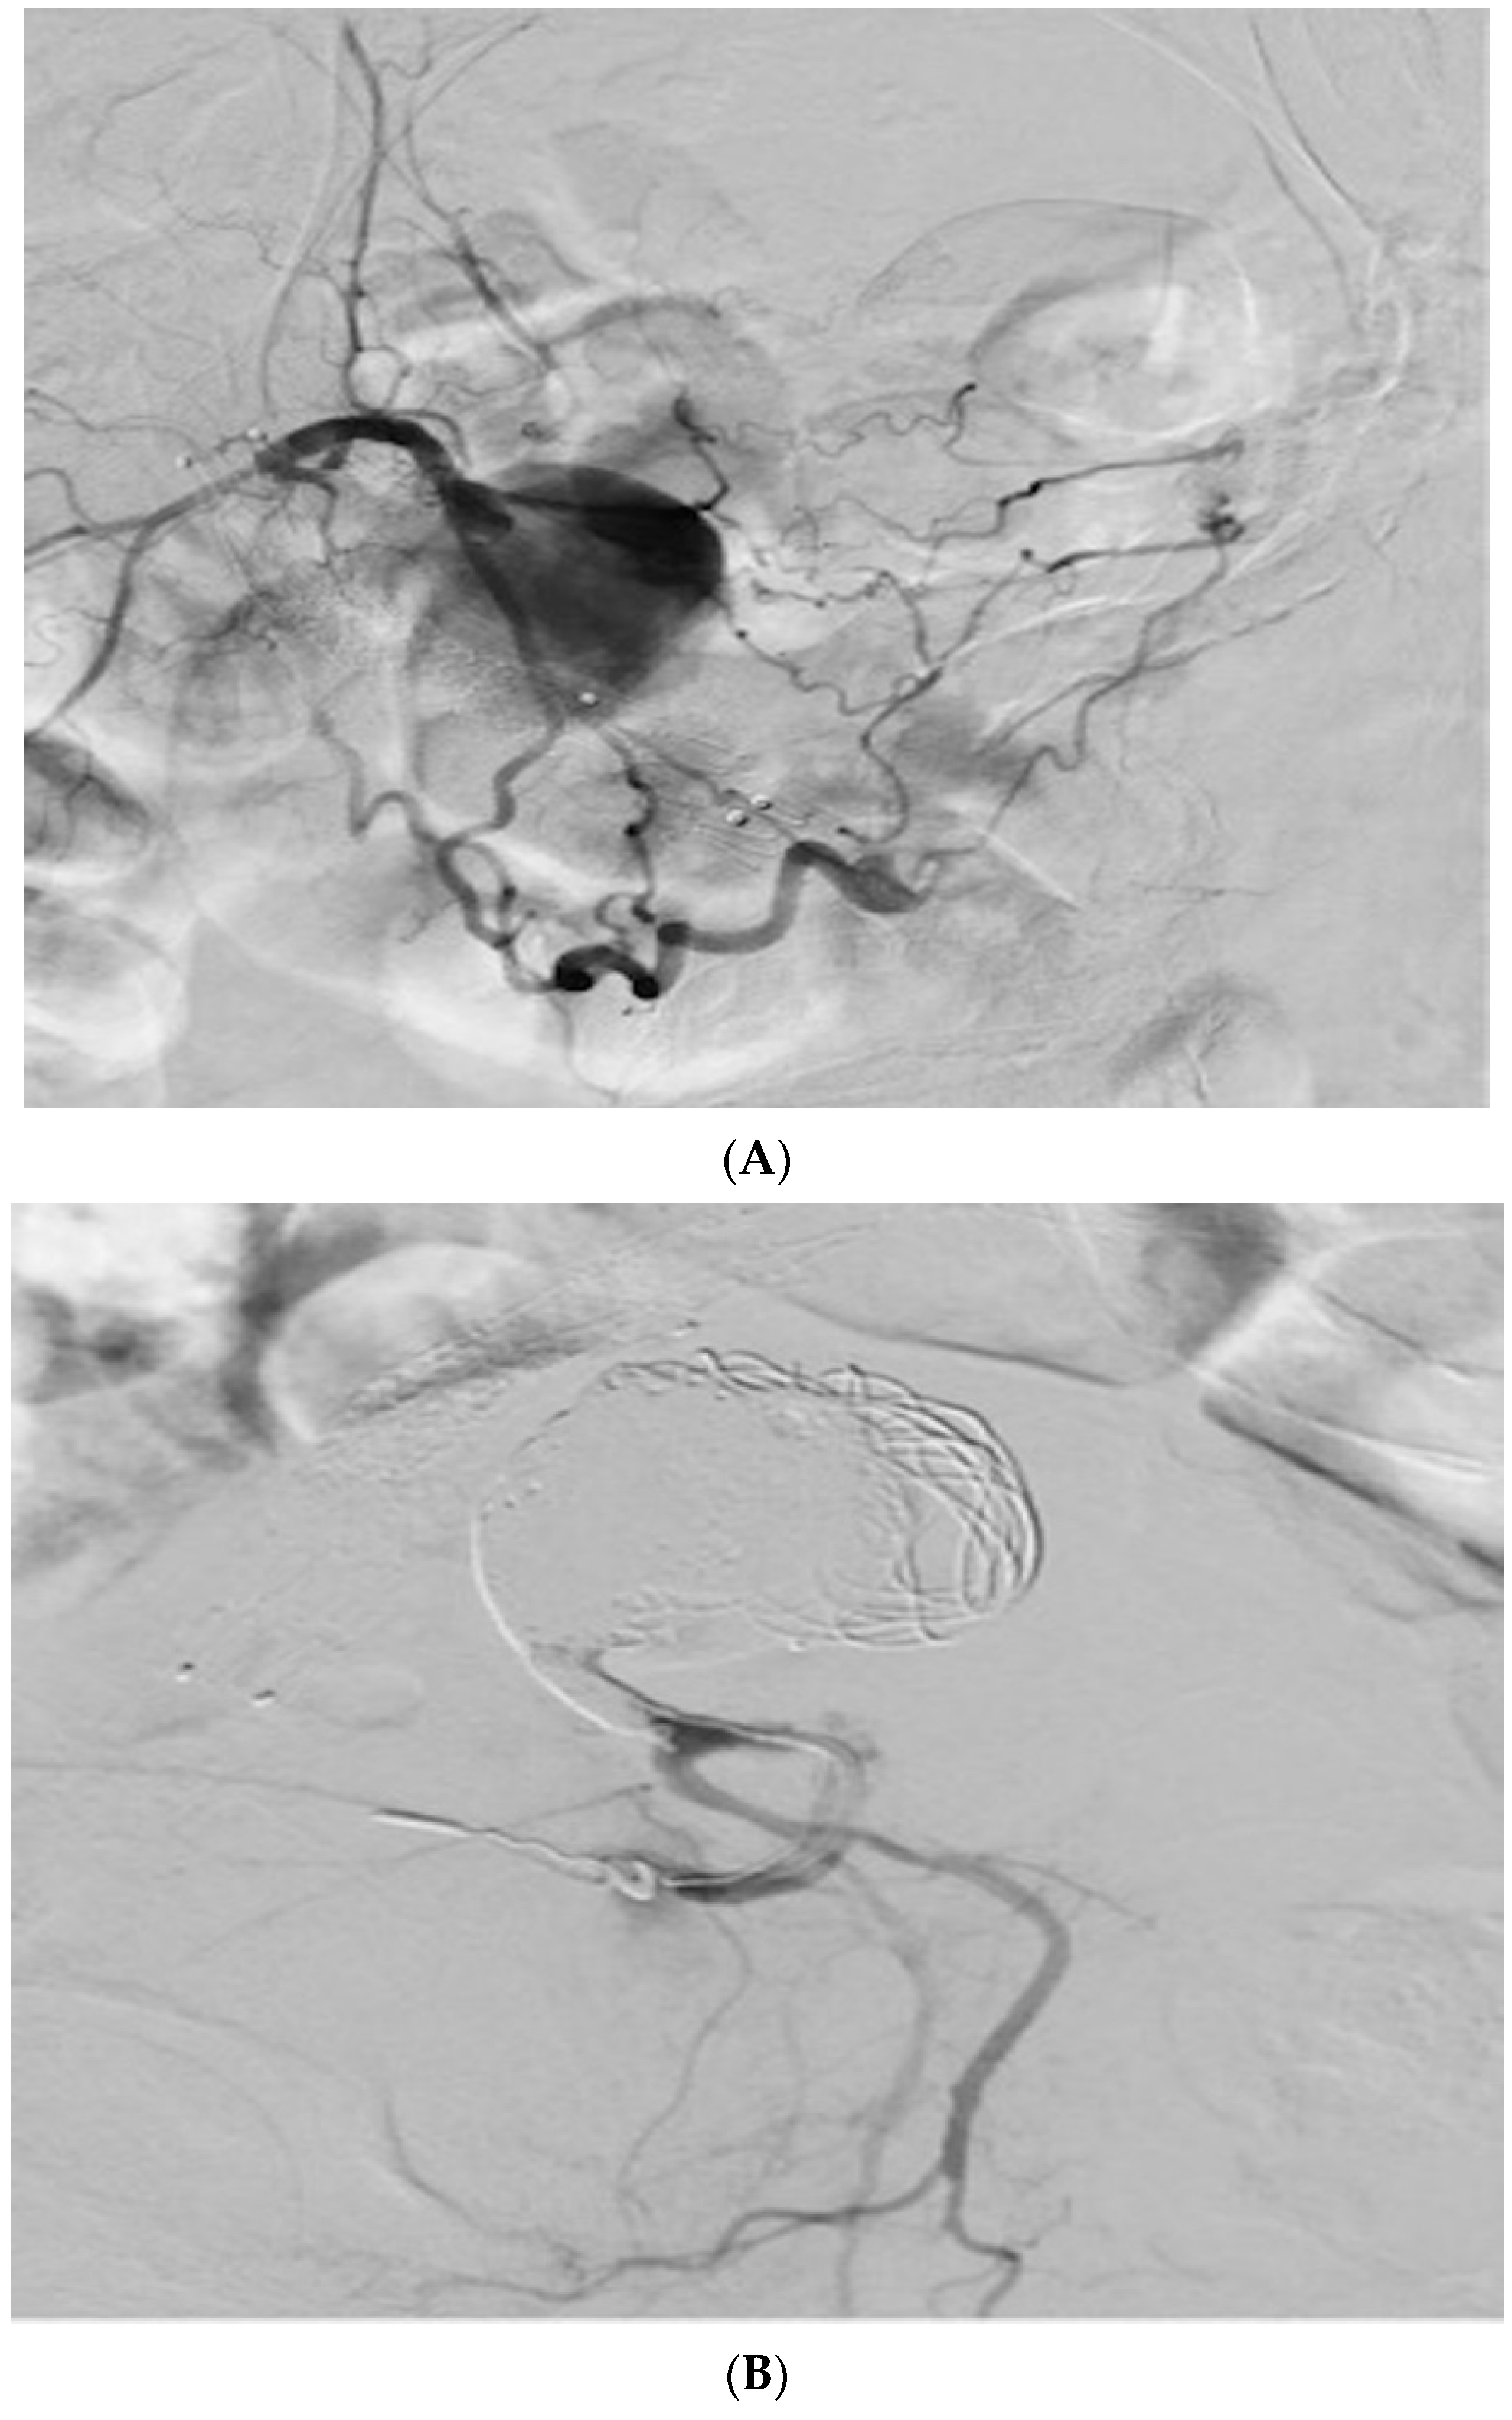

2. Case Presentation